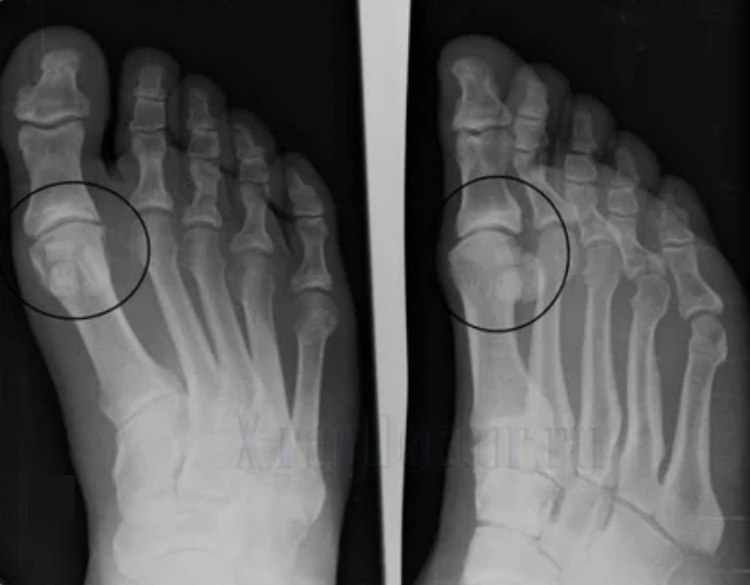

Para facer un diagnóstico, os reumatólogos examinan os síntomas do paciente e prescriben un exame x -ray. A maioría das veces, a radiografía úsase en 2 proxeccións. O Doutor examina a presenza de trastornos distróficos na cartilaxe hialina e nas articulacións óseas. Cando a brecha articular é reducida, os ósos están deformados ou aplanados, hai formacións císticas na superficie da cartilaxe, os osteófitos son signos obvios de artrosis. Durante a inspección, a artrose mostra a inestabilidade da articulación: o eixe das extremidades e a subluxación é perturbado.

Moitas veces unha imaxe x -ray non pode proporcionar información completa sobre o estado da articulación. A tomografía informática prescríbese para un estudo máis exhaustivo e é eficaz examinar os ósos. A resonancia magnética úsase máis a miúdo para examinar o tecido brando.